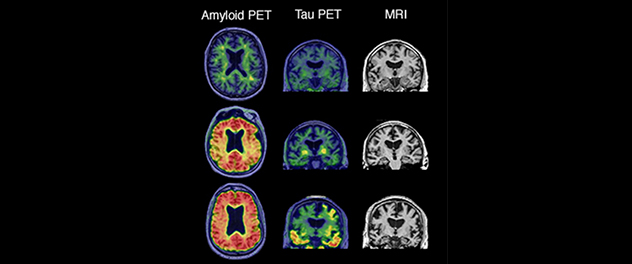

Three brain scan panels showing amyloid PET, tau PET and MRI results

Projects in Mayo Clinic's Aging and Dementia Imaging Research (ADIR) Lab focus on neuroimaging to diagnose Alzheimer's disease and related dementias before symptoms occur to treat the disease more effectively.

The ADIR lab uses modern brain-imaging modalities including amyloid positron emission tomography (PET), fluorodeoxyglucose (FDG) PET, tau PET, anatomic magnetic resonance imaging (MRI), diffusion imaging, perfusion imaging, task-free functional MRI and magnetic resonance spectroscopy, along with clinical, psychometric, genetic and neuropathologic information.